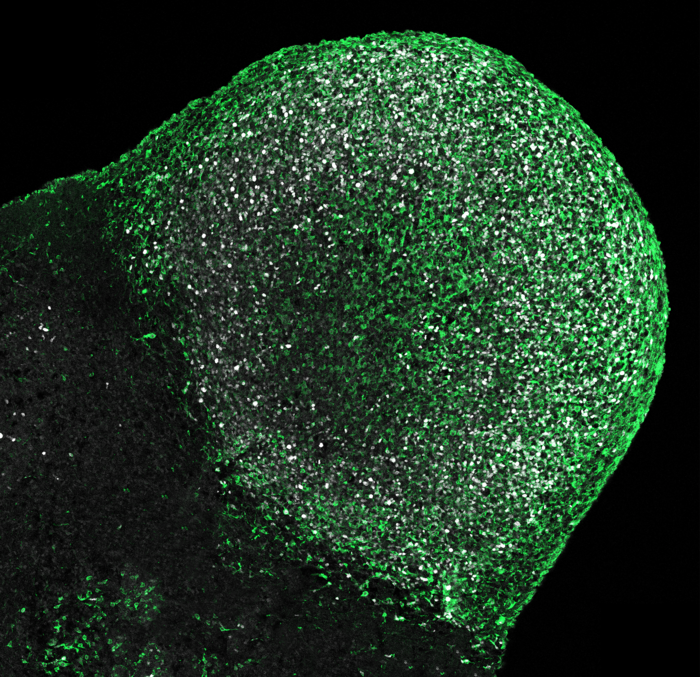

With the help of cerebral organoids, IMBA scientists were able to ascertain that Tuberous Sclerosis, a rare neurodevelopmental genetic disorder, arises developmentally rather than only genetically. With these patient-derived laboratory models of the human brain, they pinpointed the origin of the disease to progenitor cells specific to humans. The findings, now published in Science , further show that the pathology of diseases affecting the human brain could only be well understood using human-derived brain organoid models.

In many affected patients, TSC manifests in the form of severe epilepsy and psychiatric symptoms like autism and learning difficulties. Morphologically, TSC is characterized by well-described signs often found in the brains of patients. Among those are benign tumors present in a defined area of the brain, as well as lesions in the brain cortex, or “cerebral mantle”, called “tubers”. For a long time, both morphological aberrations have been attributed to a genetic cause. However, results from the analysis of patient samples diverged from the prevalent theory, mainly with regards to tubers. “To study Tuberous Sclerosis, we developed cerebral organoid models of the disease: three-dimensional cell cultures that we use to model the brain and that we can derive from any patient,” explains co-corresponding author Nina Corsini, Research Associate in the Knoblich Group at IMBA.

For the study led by Corsini and Knoblich, the team grew brain organoids from several affected patients, a method that allows to investigate molecular and cellular mechanisms that existed in the patients’ brains at some point during development. “With this approach, we found that, like in the patients’ brains, the organoids grew tumors and had disorganized areas that resembled patient tubers,” explains Oliver Eichmüller, the first author on the study. However, recapitulating the pathophysiology of a disease is only the first step towards designating the culprit: “By digging further into the causes, we found that both of these abnormalities were triggered by the excessive proliferation of a cell type specific to the human brain,” states Eichmüller . These cells were termed Caudal Late Interneuron Progenitors, or CLIP cells. They are cells found during the developmental stage of human brains but not in animals like mice. “Our study shows that our brain is very complex – much more complex than the brains of most animals.” , says Corsini.